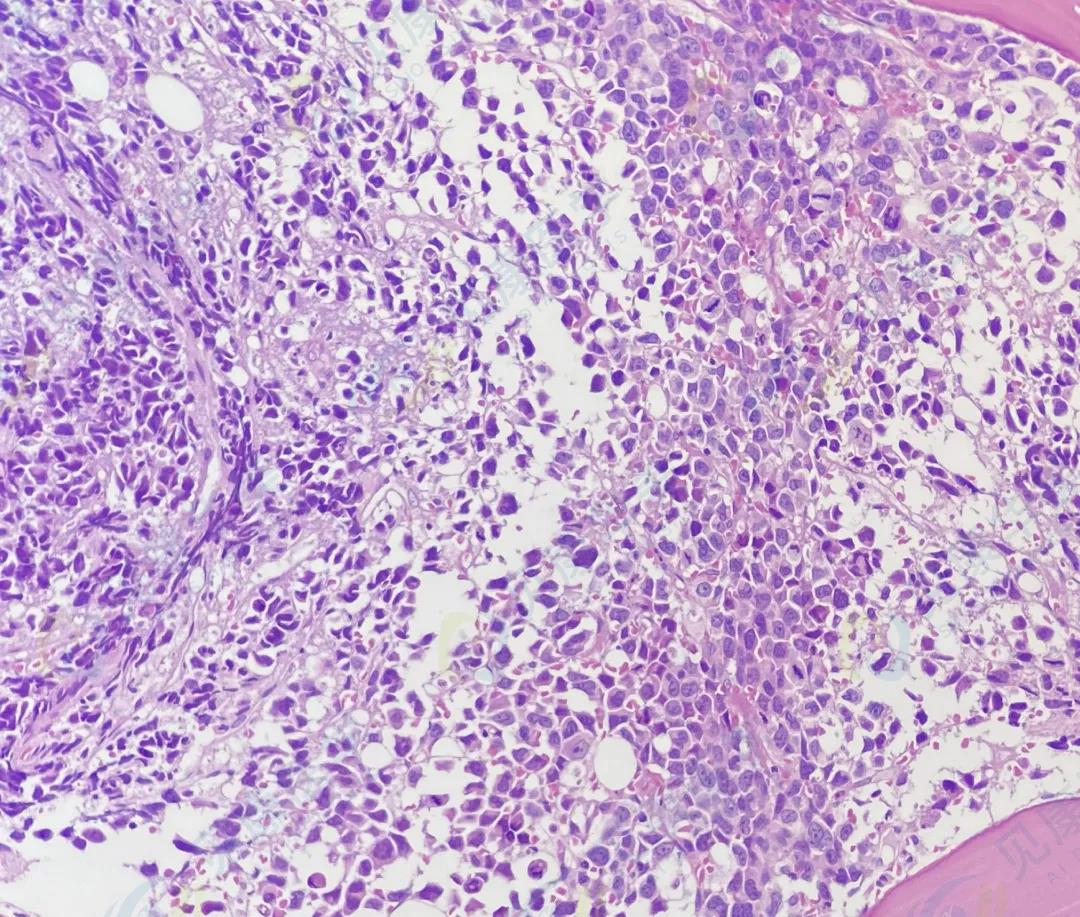

【形态学病例分享】第二十九期

患者基本信息:

男,54岁。

血常规:

病理活检

HE

诊断结果

多发性骨髓瘤

作者:田欣 张静芳